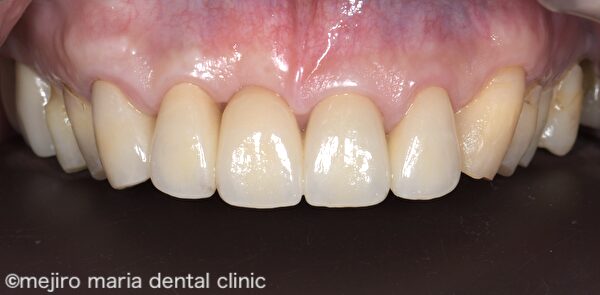

上記After 画像を見ると、歯肉形態が概ね生理的な状態に改善している事がわかります。この状態で歯肉の形態を整えながら治癒を待ち、約6ヶ月後に適合の良いブリッジを作製し装着しました。

結合組織移植術(CTG)を行った後の歯肉は、安定するまでに半年近くかかると言われています。移植した歯肉は多少小さくなって、最終的なボリュームへと落ち着きます。治癒を待つのと並行して、歯肉の形をブリッジのポンティックが収まるような形態に整え、最終補綴物を作製、装着しました。歯肉の形態が生理的な状態へと改善されたことで、清掃性も上がり、審美性も高めることができました。